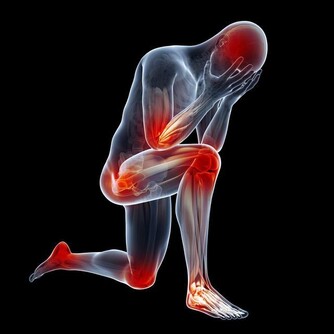

下蹲運動能夠治病強身的原理 人蹲下去,身體變成三折疊,被擠壓的血管收縮,氣血沖向全身未被擠壓的血管,迫使它們擴張、鼓起來;人一站起來,全身氣血又沖向原來被擠壓的血管,為它們灌滿血液;在這樣的一蹲一起、一壓一放、一沖一回的氣血往復運動中,就像涮瓶子一樣,使全身血管得到了反復沖洗,使血管軟化、加快血液迴圈和體內的新陳代謝、啟動免疫系統,增加了高密度膽固醇、靈敏了壓力感受器、把一些有害、有毒的代謝產物可迅速得以清除,人體自然就健康了。 下蹲可以激發經絡功能 雙腳是運行氣血、聯絡臟腑、溝通內外、貫穿上下的十二經絡的重要起止部位;加上奇經八脈,下蹲運動可以自然地激發這近20條經脈的經氣。 下蹲運動的其他作用和好處: ◇與長壽有關 對一些百歲健康老人的生活方式調查發現,他們從事田地耕作,蹲在池塘邊淘米、洗菜、洗衣服、廁所也是蹲的…這就強健了他們的腰腿,達到了祛病除疾的作用。 ◇強健關節和骨骼 下蹲可增強腰、髖、膝和踝關節的活動範圍,增強膝關節的靈活性,延緩關節的老化,關節如果活動少,會使骨骼變得脆弱,鈣就會流失到血液中,而且會積存在腎臟和膀胱中,造成排尿困難以及細菌繁殖等不良後果,所以經常使用和活動關節是永保年輕的關鍵。 ◇可以增強肌肉力量 常做下蹲運動可以增強肌肉力量,尤其是下肢的肌肉力量;兩條腿的力量增強了,可有效預防跌倒,走路時您會感到身體輕鬆,且生命充滿活力。 人體肌肉如果適度使用,將會更發達,但廢棄不用或過度使用就會退化。 ◇可改善血管功能 可以擴張微、小動脈血管,減少心臟外周阻力,可以改善微、小動脈血管壁的彈性,有效地降低血壓。 ◇可以降低血脂 下蹲運動通過刺激經絡系統,可使脾經運化功能增強,促進血管壁粥樣斑塊的分解,降低血液的粘稠度,減少血液中甘油三酯和低密度脂蛋白,增加高密度脂蛋白,促進脂代謝,進而改善血管的彈性,有效防治動脈粥樣硬化,對預防心、腦血管意外的發生有重要意義。 ◇可以促進新陳代謝 下蹲運動主要靠兩條腿的屈伸來支撐軀幹以上身體的重量;當下蹲時,身體的重量向下壓擠腿部肌肉中的血管,加快下肢的靜脈血液流向心臟;當身體起來時,解除了身體重量對下肢肌肉的擠壓,從心臟泵出來的動脈血快速進入下肢,如此反復下蹲、起來、再下蹲,有如「唧筒」的作用,加快血液迴圈和新陳代謝;血液迴圈加強了,回心血量增加,有效地改善心肌的血液供應和新陳代謝;血液迴圈加強了,胰腺等臟腑器官的營養與氧氣供應得到充分改善,胰島素分泌細胞的功能恢復正常,可有效地控制糖尿病。 ◇增強性功能對 下蹲運動可以強健大腿內側的肌肉,包括直接與性能力相關的長收肌,另外由於能使容易淤積在此的血液和淋巴液回流,也就促進了生殖器官的活躍,人到中年後性功能會逐漸減退,如果能長期堅持下蹲,性功能會逐漸提高。 ◇減肥效果明顯 下蹲能消耗很多熱量,可以減掉身上多餘的脂肪,特別臀部和大腿堆積的脂肪;另外下蹲時由於擠壓腹部,想知道自己一生愛情財運如何,添加大師微信:byou66 ,免費給你算命!促進腹腔臟器周圍的脂肪燃燒分解,減少脂肪的積累,亦可刺激胃腸的食物消化,促進消化酶的分泌。 ◇鍛煉可以使精神放鬆 可以暫且拋開煩惱、放下生活的壓力、使人的精神得到放鬆,調節情緒,增加生活樂趣,這對人的身心健康都有好處。 ◇能延緩大腦的衰退 如果腿衰老了(主要原因是肌肉、骨骼、關節的老化),大腦也會隨之衰老;腿衰老後人的活動減少,感官接受新資訊的機會減少,來自外界的刺激少了,大腦細胞也就不再活躍,人就會變得癡呆起來;下蹲可以加強腿的活動能力,增強和外界接觸,不但能夠延緩大腦的衰退,而且可以進一步增智開慧。 動作要領 下蹲的姿勢:正確的姿勢應該是從動作開始到結束,頭部到腰部的軀幹要始終保持筆直伸展的狀態,臀部要向身後撅起。 開始姿勢:要全身放鬆,兩腿分開,略比肩寬(或與肩同寬),自然地站立;腳尖的方向基本是倒八字形,以腳的第二趾的方向為准;下蹲時,膝蓋的方向要在第二趾的延長線上,這樣做起來比較自然而不吃力。 結尾姿勢:膝蓋彎曲,直到大腿與地而平行為止(視乎各人體力,老年人或初練者可先取用半蹲或1/4蹲);在完全蹲下時停頓片段最能鍛煉肌肉。 向上站起時的姿勢:向上站起時的要點是感覺整個腳掌在向下推壓地面,直立站起。 下蹲時的速度:1次下蹲的速度(時間)大致標準是5秒鐘1次(視乎體力,以舒適為佳),到了蹲的姿勢時,有意放慢速度更好。 呼吸方法:一邊下蹲,一邊吸氣;一邊站起來,一邊呼氣。 鍛煉的次數:注意量力而行,循序漸進,以1天做30次以上為宜;體弱的人開始少做,有體力的人可多做。 做下蹲運動的頻率:如果想維持健康或消耗脂肪的話,是應該每天鍛煉的。